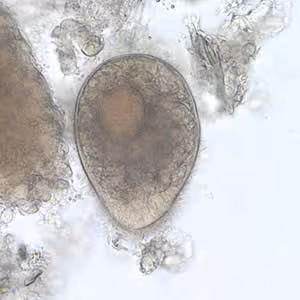

A 27-year-old woman who had been working in Laos, Thailand, and Vietnam for one and a half years was visiting relatives in the U.S. While she was in the U.S., she visited a physician for recurring abdominal discomfort, bloating, and frequent bowel movements that she had experienced over the last two months.